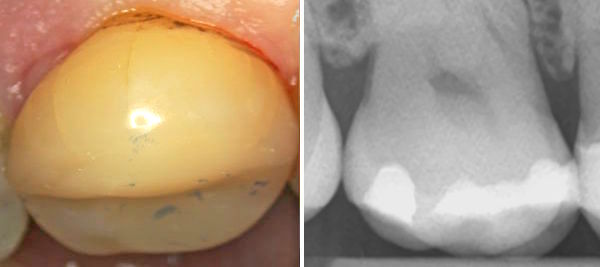

Der Patient spürt immer wieder einen leichten Kauschmerz. Der Zahn hat aber keine Karies.

Der Zahnart sieht die beiden Schmelzsprünge und die minimal undichte Stelle unter der Füllung. Er erneuert die Füllung. Aber trotzdem entsteht wieder ein Kauschmerz und dazu noch eine Kaltempfindlichkeit.

Der Zahnarzt ersetzt die Füllungen mit einen anderen Material. Aber der Kauschmerz entsteht immer wieder, auch beim Kauen auf einen Kaugummi, wenn dieser noch hart ist.

Die Kaumuskeln sind die stärksten Muskeln. Beim Kauen enstehen ja nach der Geometrie der Kauflächen senkrechte schmerzfreie Normalkräfte oder aber auch waagrechte schmerzhafte Querkräfte.

Dem Zahn fehlen die Abflussrillen. Deshalb entstehen Querkräfte. Die beste Therapie ist das Einschleifen von Abflussrillen. Dann entsteht beim Kauen eine Normalkraft statt eine Querkraft.